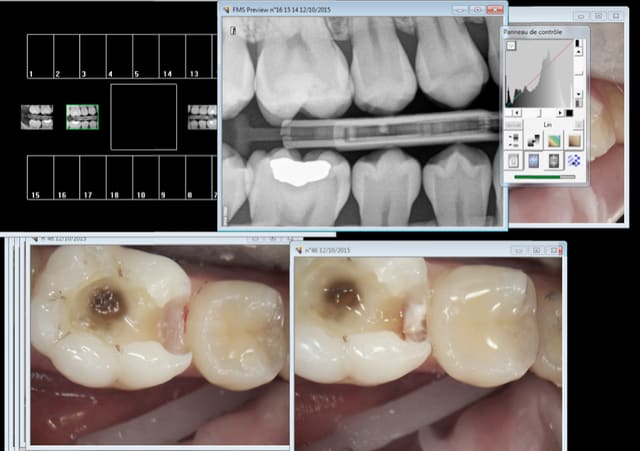

Ca endort tout ( signe de vincent) . J'ai soigné la 6.

Notez le bilan rétro coronaire indiqué dans ce cas à risque carieux faible ! -))))

Capture d e cran 2015 10 12 15.44 - Eugenol